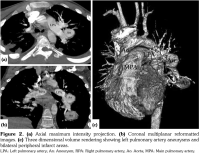

On admission, body temperature was 38.5°C. The patient had tachypnea, dyspnea, tachycardia, decrease of breath sounds in the basal regions of both lungs, and few crackling rales were heard in the left lung field. There was nearly total loss of vision in the right eye and 40% loss of vision in the left eye. Chest radiograph revealed a large left parahilar mass and peripheral infiltration (Figure 1). Computed tomography (CT) angiogram revealed two aneurysmal dilatations originating from the intraparenchymal branches of the left pulmonary artery (18x26 mm, 31x20 mm). Peripheral infarct areas were seen in basal fields of both lungs, and pulmonary embolism was present in the intraparenchymal branches of the right pulmonary artery (Figure 2). Concurrent transthoracic echocardiography showed a tripartite homogeneous hyperechogenic mass with a stalk-like structure, measuring 25x27 mm, filling most of the right ventricle, strongly suggestive of a right ventricular thrombus (Figure 3). The right ventricular pressure was within normal limits, thereby excluding pulmonary hypertension. Doppler ultrasound of lower extremities was unremarkable.

A follow-up transthoracic echocardiogram obtained after three months showed significant reduction of the IcT. Chest radiograph showed no regression of PAA. Four months after the initial admission, the patient suddenly died due to massive hemoptysis probably originating from PAA rupture. Since the family rejected autopsy, the precise etiology of death could not be established.